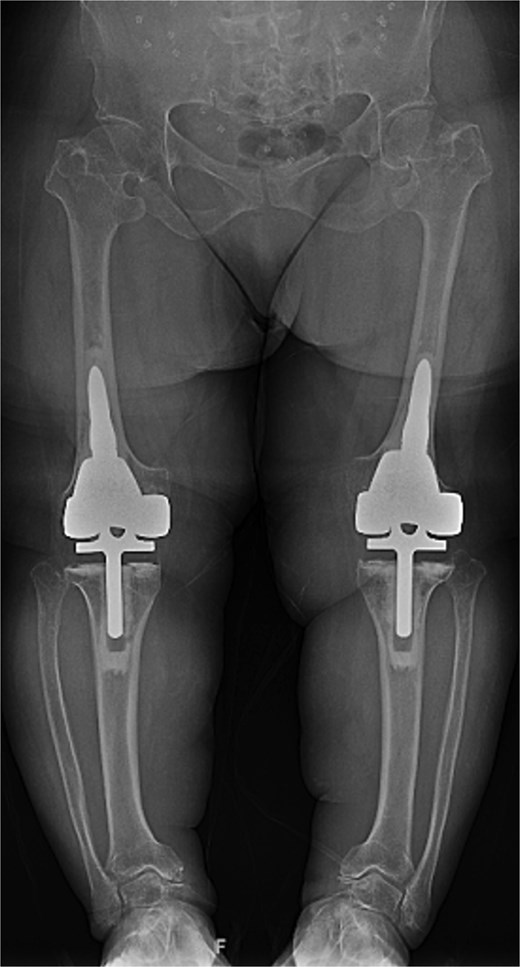

At the 2-year follow-up, the patient reported no significant pain, demonstrated a normal gait, and had active bilateral knee range of motion from 0° to 125°. There was no joint line tenderness or instability. Surveillance radiographs confirmed well-aligned and stable components with no evidence of implant failure or periprosthetic lucency (Fig. 3). At the five-year follow-up, the patient remained very satisfied with her knees and denied knee pain. On exam, her gait was slightly antalgic, but active bilateral knee range of motion remained preserved at 0° to 120°, and both knees remained stable throughout range of motion and nontender to palpation. Radiographs continued to show stable prosthetic components without evidence of implant failure or periprosthetic lucency (Fig. 4).

Two-year postoperative AP radiographs demonstrating stable, well-fixed components with appropriate alignment and no evidence of implant loosening or periprosthetic lucency.